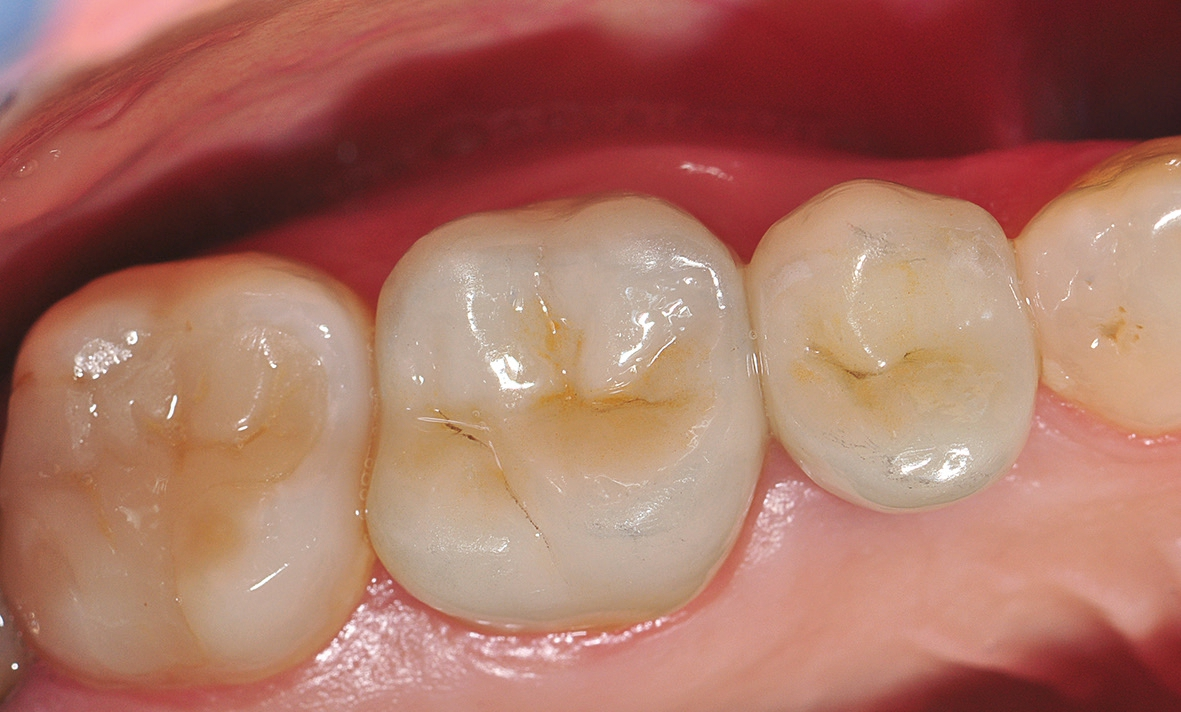

Nach einer komplikationsfreien Einheilzeit von vier Monaten konnte mit der Herstellung des definitiven Zahnersatzes begonnen werden. Hier entschied man sich konsequent für monolithische Kronen aus Lithiumdisilikat, um das Chippingrisiko so gering wie möglich zu halten [12]. Im Zuge der Implantatversorgung wurde nun auch – wie geplant – die metallkeramische Krone an 16 geschlitzt, entfernt und der Stumpf nachpräpariert. Implantatkopf und Zahnstumpf wurden daraufhin zusammen mit A-Silikon analog abgeformt. Für die geschlossene Abformung wurde die Abformkappe (impression.transfer) auf dem Implantatkopf positioniert. Ein deutliches Einrasten signalisierte den lagestabilen Sitz. Für die Modellherstellung rastete das Implantatanalog (lab. replica) ebenso in die integrierte Abformkappe ein. Nach der Herstellung des Meistermodells konnten die beiden Kronen im digitalen Workflow CAD/ CAM-gestützt gefertigt werden. Nach Ausarbeitung, Bemalung und Glasur waren die beiden Kronen für die definitive Zementierung bereit. Die klinische Einprobe der Restaurationen verlief erfolgreich, sodass die Kronen nacheinander mit selbstadhäsivem Befestigungskomposit eingegliedert werden konnten.

Auch wenn die Sofortimplantation mit dem ceramic.implant nicht Teil des offiziellen Indikationsspektrums ist, erwies sich das einteilige keramische Implantat wie schon mehrfach in anderen dokumentierten Fällen als schnelle, ästhetische und sichere Versorgungsform. Natürlich müssen alle Grundvoraussetzungen für eine Sofortimplantation gegeben sein. Eine penible Risikoanalyse sollte deswegen im Vorfeld immer durchgeführt werden. Das Implantationsgebiet muss entzündungsfrei, genügend Knochen in der Schaltlücke vorhanden und eine gute Mundhygiene sowie Compliance von Patientinnen und Patienten gegeben sein. Ein dicker Gingivatyp erhöht signifikant die Wahrscheinlichkeit für stabile gingivale Verhältnisse [13]. Aber auch Allgemeinerkrankungen und die etwaige Einnahme von Medikamenten entscheiden darüber, ob eine Sofortimplantation vertretbar ist oder nicht [14,15]. Im Zweifelsfall sollte die Entscheidung auf eine geschlossene Einheilung fallen.